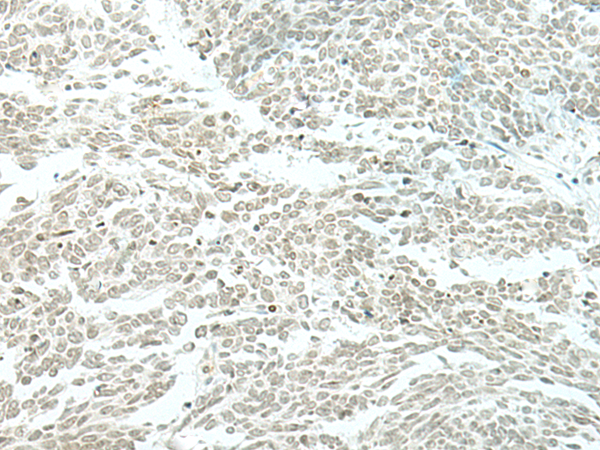

分类: 科研抗体货号: P06470别名: EVI1; MDS1; KMT8E; PRDM3; RUSAT2; MDS1-EVI1; AML1-EVI-1应用: WB,IHC反应种属: Human, Mouse